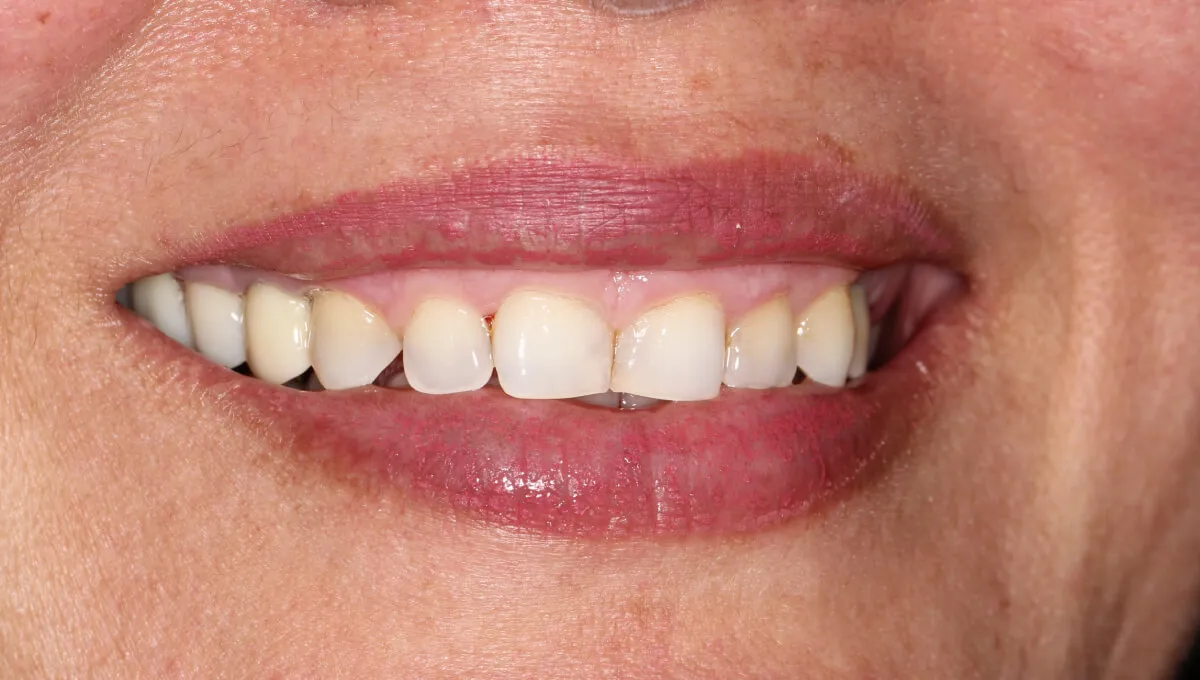

This lady received two dental implants and a bridge to replace her upper missing teeth. We restored her teeth, smile and boosted her confidence. She is very happy with the results and smiles with higher confidence.